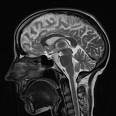

El rastro cerebral del autocontrol

La capacidad para controlarse reside en una zona del cerebro distinta a la responsable de generar acciones intencionadas o la que se activa al seleccionar entre diferentes alternativas. Según un estudio publicado en 'The Journal of Neuroscience' la identificación de esta área podría ayudar a explicar algunos trastornos psiquiátricos en los que el autocontrol está alterado.